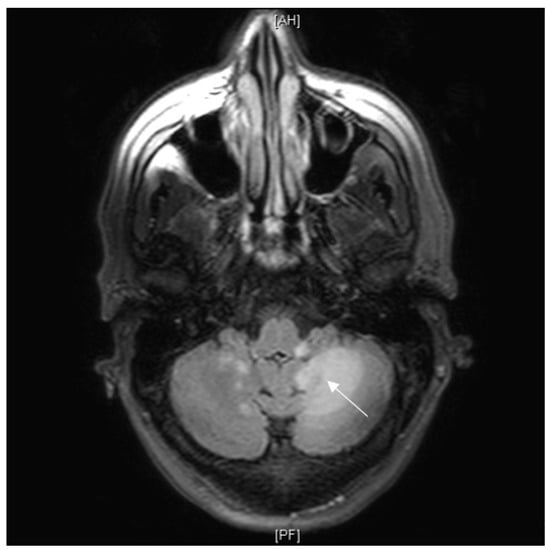

3.7.1. Case Description